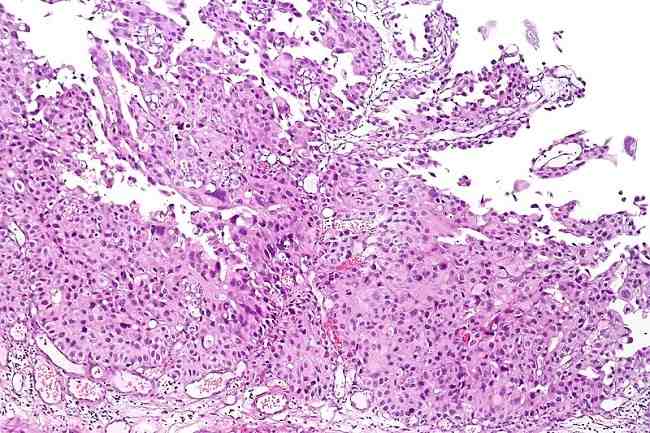

Berdasarkan variasi histologinya, karsinoma urotelial dibagi menjadi nested, microcystic, micropapillary, lymphoepithelioma-like, plasmacytoid, sarcomatoid, giant cell, lipid-rich, clear cell, neuroendocrine carcinoma, karsinoma urotelial dengan ciri squamous, karsinoma urotelial dengan ciri glandular, primary squamous cell carcinoma, dan primary adenocarcinoma.[2]

Karsinoma urotelial juga dibagi berdasarkan derajatnya, yaitu low grade dan high grade. Gejala tersering yang dialami pasien adalah hematuria. Nyeri juga termasuk dari gejala penting dalam karsinoma urotelial.[2,3]